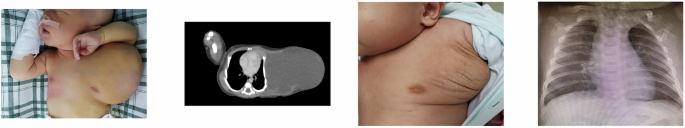

Typical images of patients in the two groups are shown in Figs. 1 and 2.

After the treatment, the size of the lesion reduced and chest radiography showed relief of the chest wall compression.